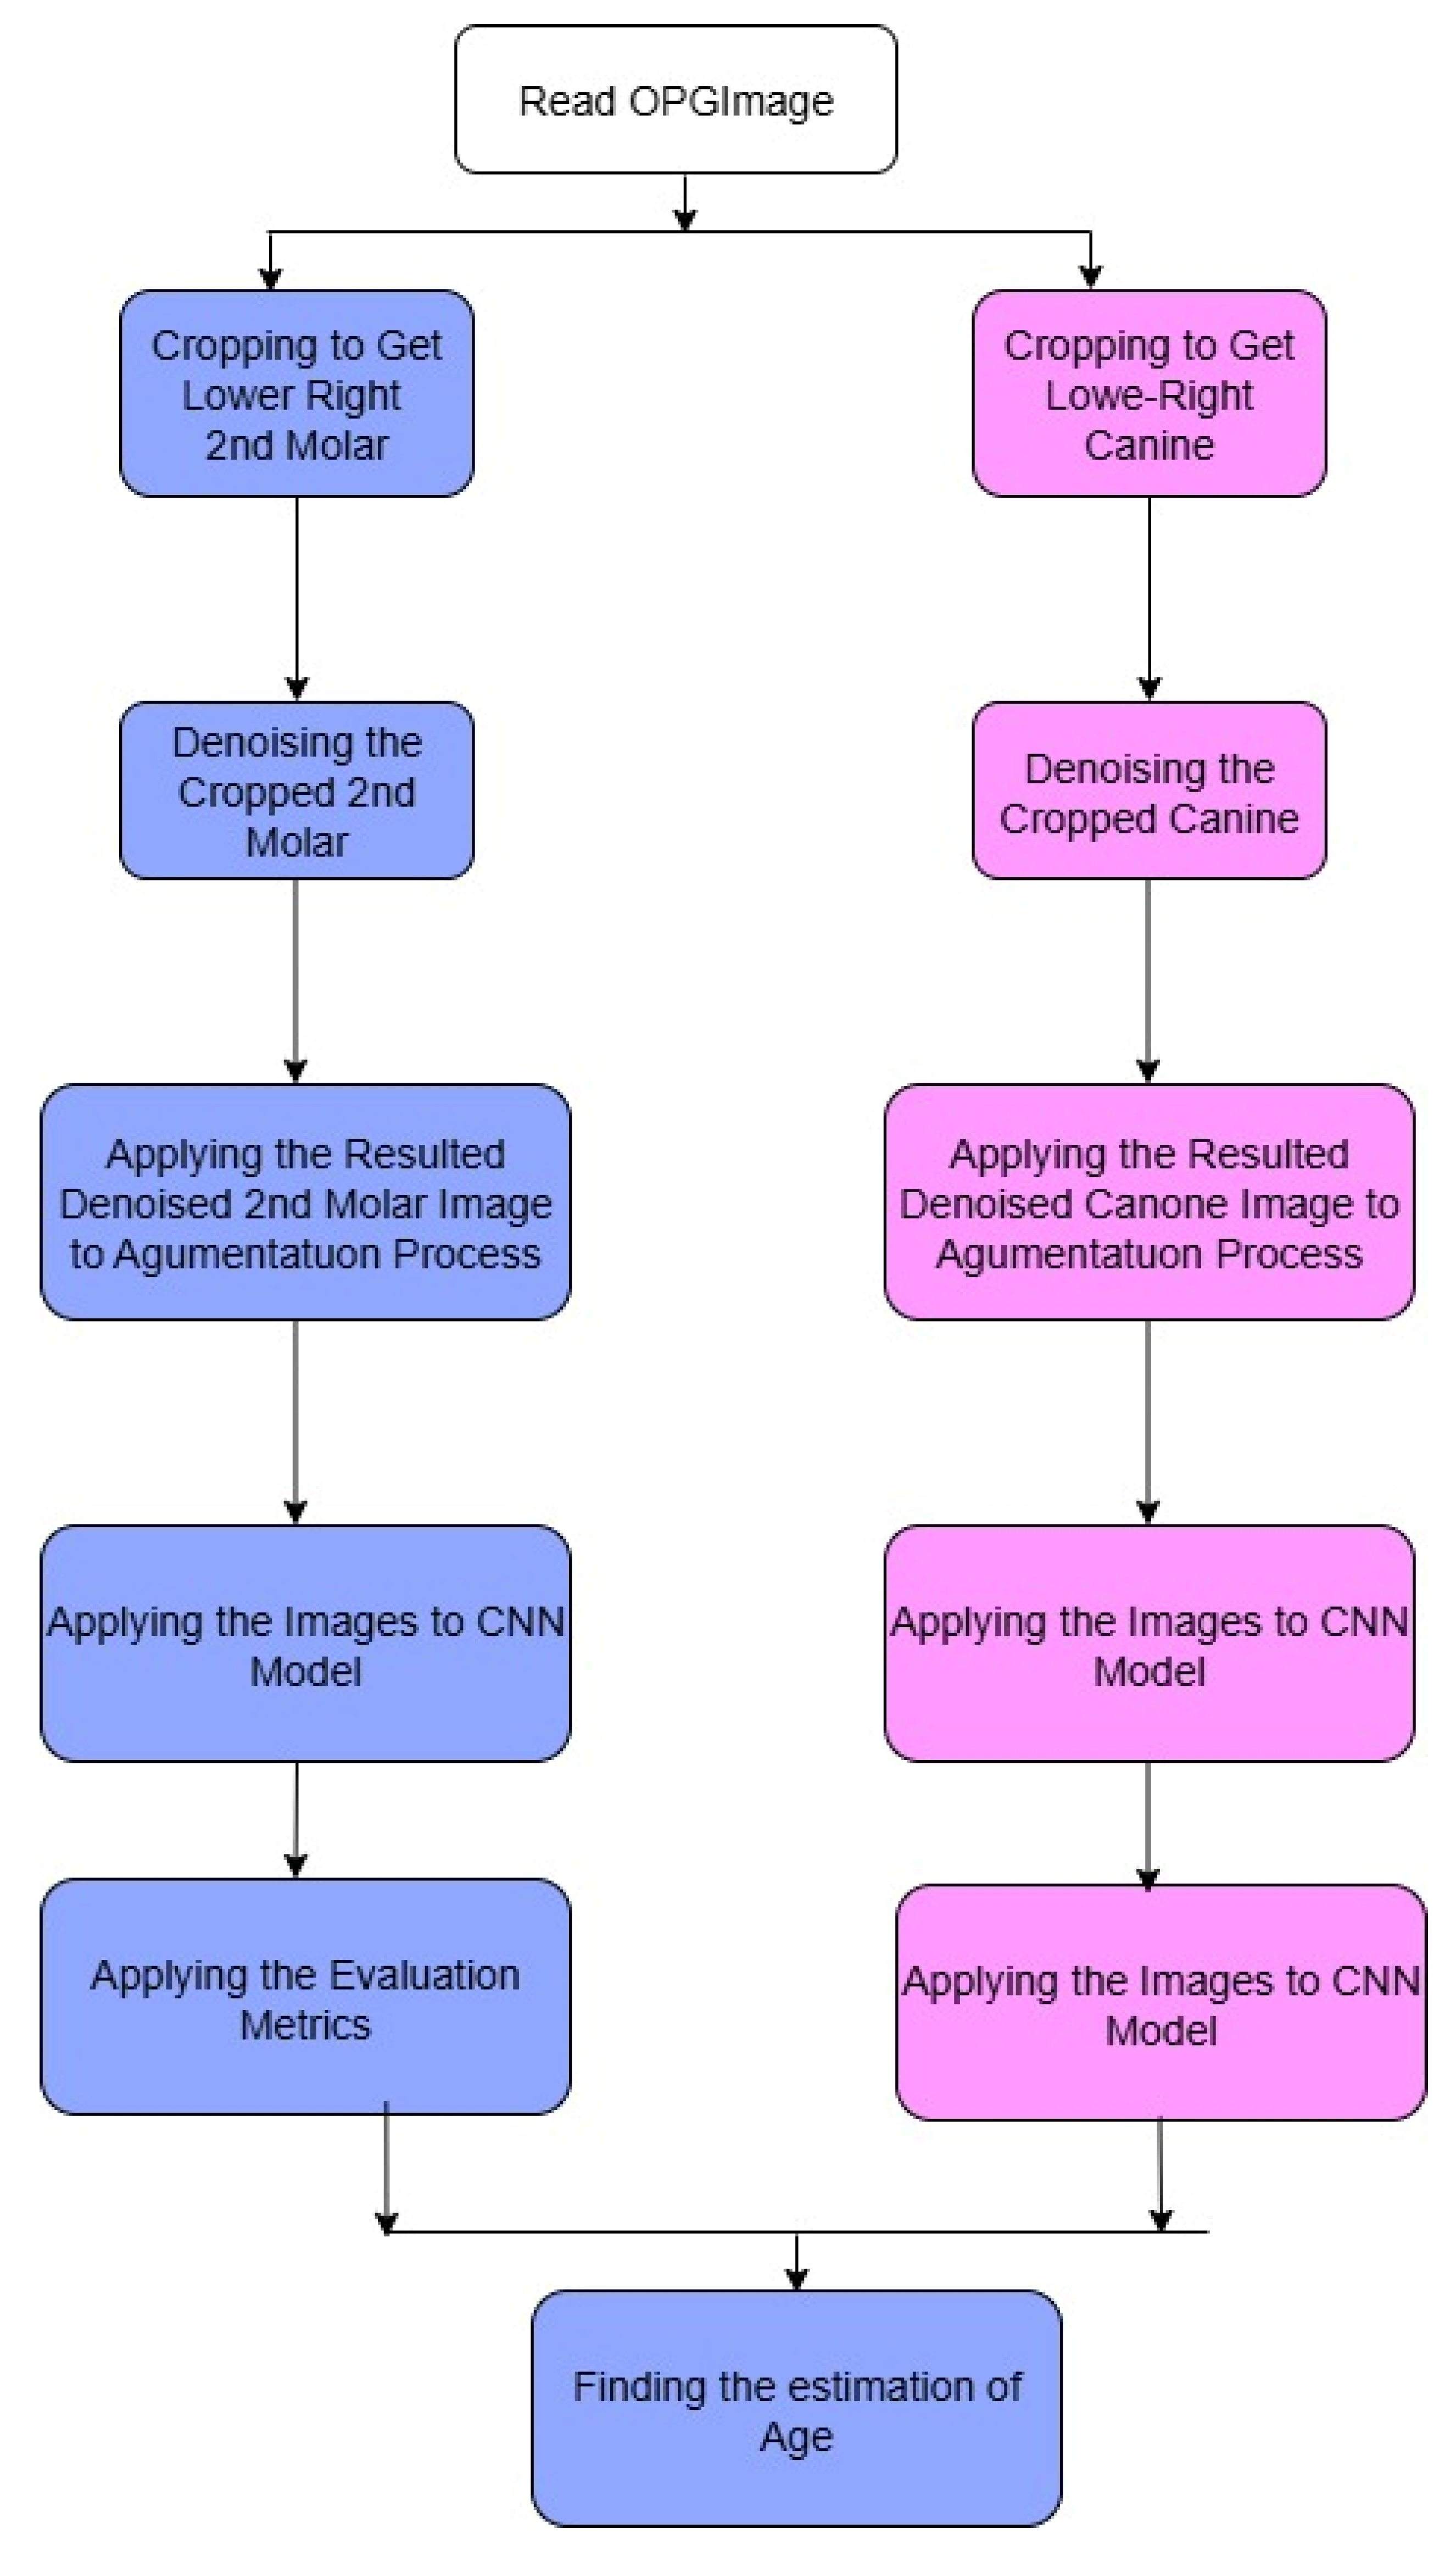

Figure 3. As in any pipeline, the input OPG image goes through a preprocessing step, which includes cropping the image to the relevant regions. In this case, the relevant regions are the areas containing the canines and the molars, henceforth referred to as ROIs. In the subsequent steps, each ROI is processed through the appropriate branch of the CNN; the canine crop goes through the branch dedicated to canine classification and the molar crop goes through the branch for molar classification. The classification of Demirjian stages is carried out in each branch after going through several convolutional and pooling layers in order to extract the relevant features. The model can specialize for the different anatomical features of canines and molars because of the separate pathways.

2.5.1. Strategy of Predictions

The prediction strategy involved a sequential deep learning design using two CNN models trained independently. Model A (the first model) was constructed to identify the developmental stage of the lower second molar from the cropped ROI of the OPG. The lower canine’s developmental stage that corresponded to the anticipated second molar stage was then predicted using the second model (Model B), which was fed the second molar image.

The second molar is initially assessed for maturity before being employed as a predictive signal to forecast the development of the lower canine in this two-stage architecture, which replicates a clinically realistic workflow. This pipeline makes use of the spatial-architectural properties that CNNs have learnt from the related radiographic textures and morphology, in contrast to traditional approaches that depend on statistical correlations or manual assessments. The result of Model B is a classification of the lower canine into one of the Demirjian stages (C–H) (

Appendix A), enabling a classification of developmental maturity with minimal human input. This approach eliminates the need for manual feature extraction or supplementary imaging, enabling a completely automated decision-support framework based solely on OPG images.

Figure 4 shows the complete architecture prediction pipeline. The duplication of the CNN input representation may have been misleading. We show two input- arrows to the CNN model (indicated by pink) to symbolize both canine and molar cropped images when are passed through the same CNN architecture for classification independently. These two streams are not identical; instead, they correspond to two kinds of ROI crops performed in distinct contexts of the pipeline.

Figure 4.

The pipeline workflow of the proposed model.

Figure 4.

The pipeline workflow of the proposed model.